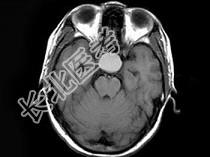

- 单项选择题男,19岁, 视力模糊1周,MRI检查如图所示应诊断为 ( )

A、颅咽管瘤

B、脑膜瘤

C、垂体瘤卒中

D、脑膜膨出

E、未见异常